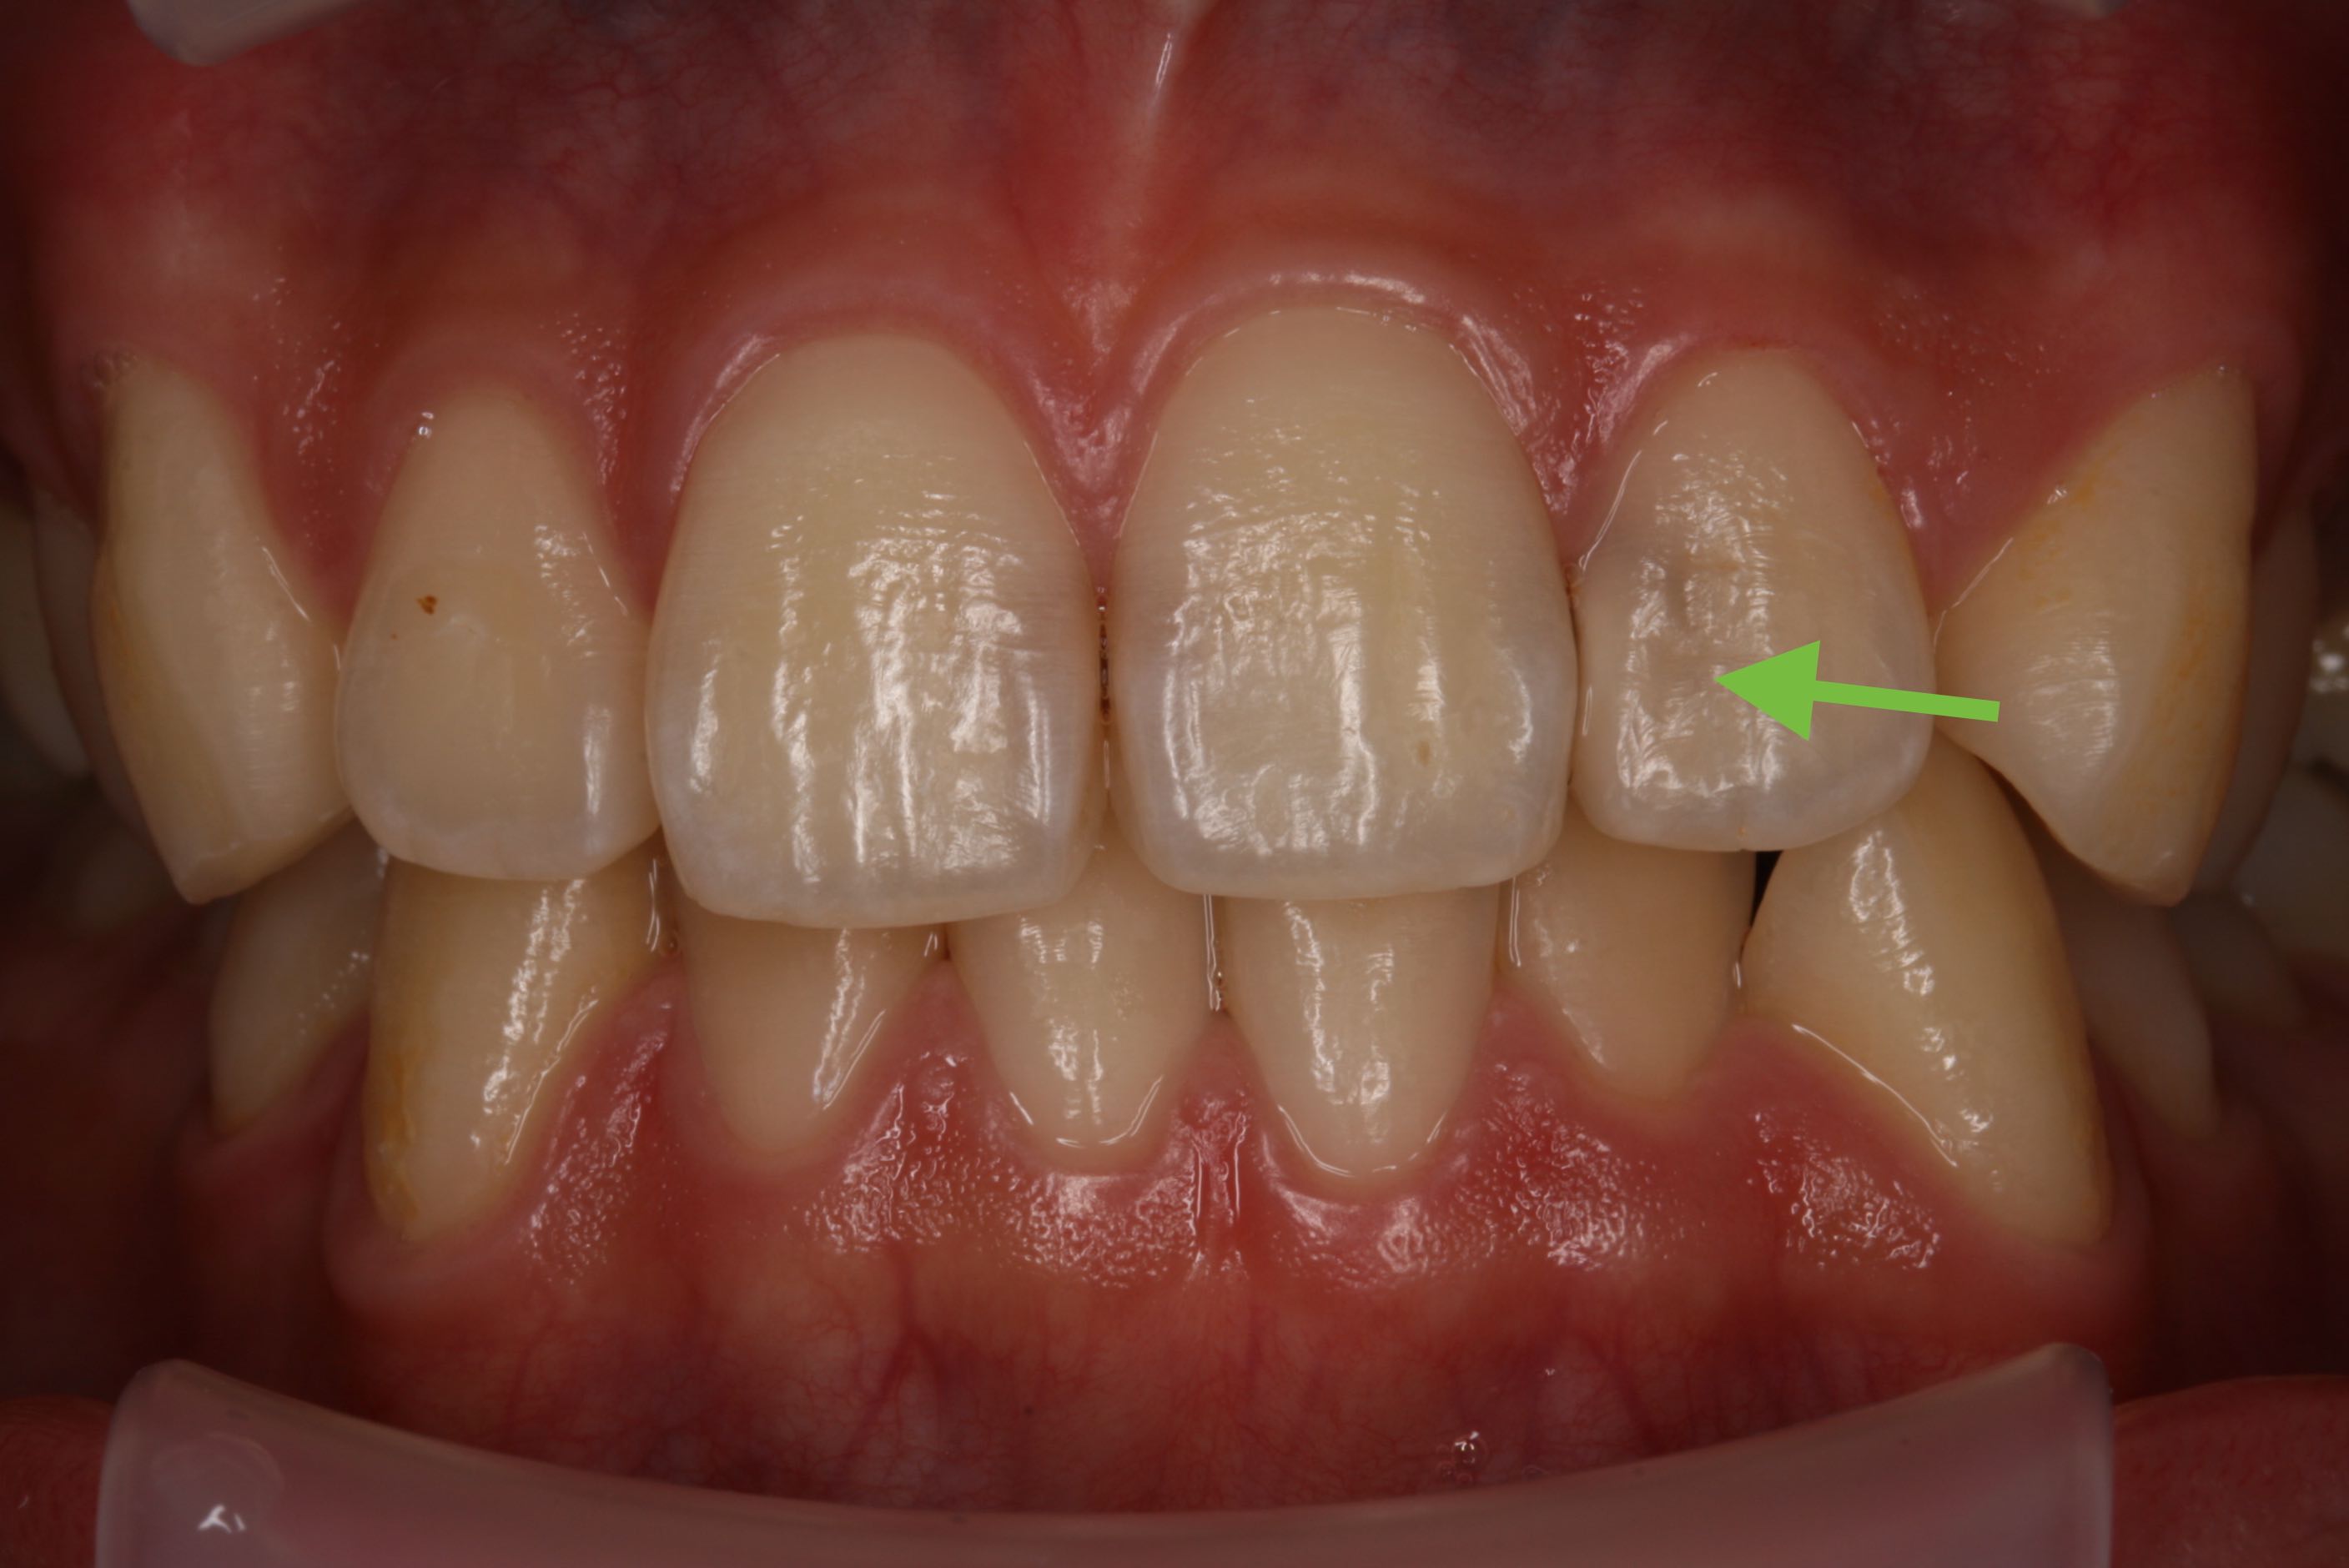

ティーンエイジャーの歯はまだ完全に成熟していないので、虫歯の穴は小さく見えても深く大きく広がりやすく、中の神経にまで進んでいることがあります。

寿命を80歳前後と考えると、ティーンエイジャーは70年近くこの歯を管理しなければなりません。